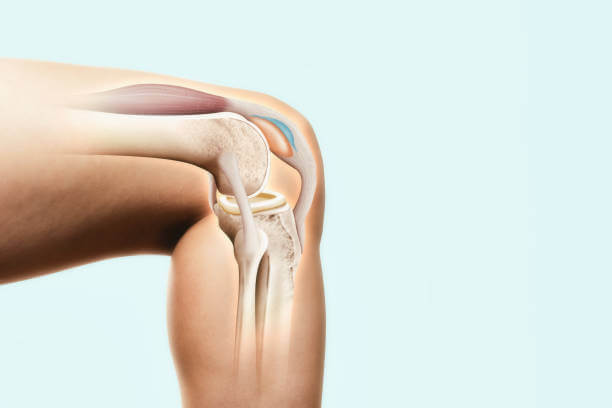

무릎에 물이 무엇인지 설명하자면 관절액입니다. 관절은 연골에 영양을 공급하고 체중을 분산시켜 관절을 보호하는 점성 유체로 채워져 있습니다.

관절액은 관절을 둘러싸고 있는 주머니 안에 있는 활액막이라는 조직에서 분비되며 생산과 흡수를 반복하면서 항상 5cc 정도의 일정한 양을 유지합니다.

그러나 무릎 관절에 염증이나 손상이 발생하면 활막으로부터 무릎을 보호하기 위해 많은 양의 관절액이 분비되며 생성되는 양보다 흡수되는 양이 많습니다. 이 상태는 무릎 활액막염라고도 하며 무릎에 물이 차 있는 상황입니다.

무릎 관절에는 끈적끈적한 관절액이 분비되어 부드럽게 움직일 수 있습니다. 이 관절액은 활막에서 분비되며 관절을 적셔 마찰을 방지하고 뼈의 마모나 손상을 방지합니다.

그런데 활막에 염증이 생기거나 외부 충격이 가해지면 활액이 과도하게 분비가 되는데 활액이 너무 많이 분비되면 제대로 흡수되지 못할 때 고여서 무릎에 물이 찬 것을 말합니다. 그러니까 관절액이 과도하게 생성되는 상태를 의미하며 활액막염이라고 합니다.